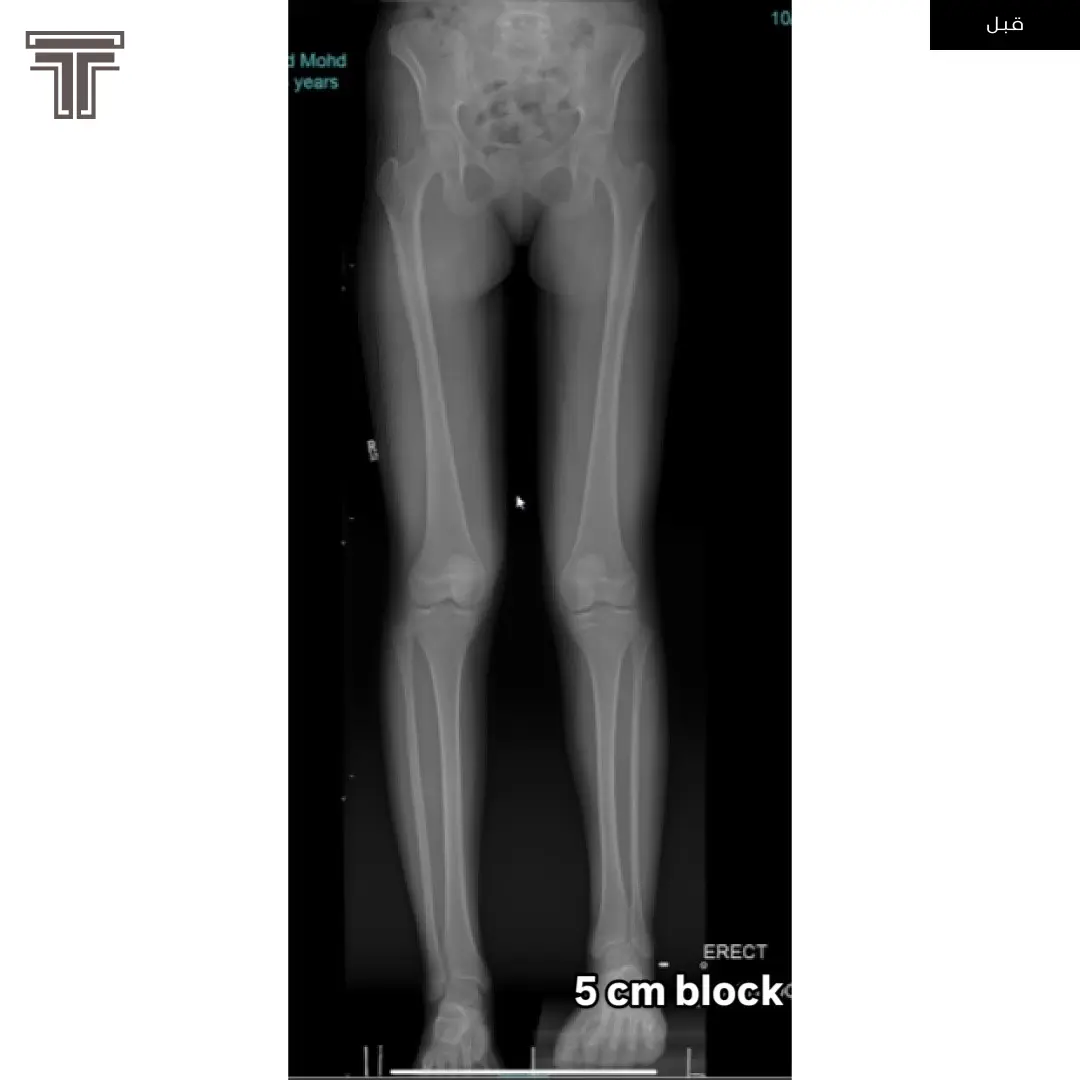

عندما تهمل خلوع الورك الولادية لعمر كبير يصبح علاجها وارجاعها صعب ويتطلب عملية استبدال للمفصل. وفي مثل هذه العمليات وتحديدا في استبدال مفاصل خلوع الورك الولادية يتطلب تقصير في طول الفخذ لتجنب المضاعفات.